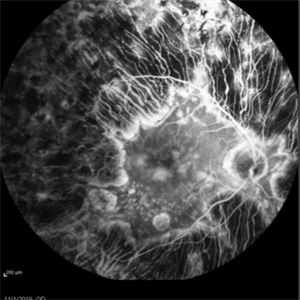

Adenocarcinoma Arising from CHRPE

49-year-old female referred for presumed ocular melanoma. On examination was noted to have darkly pigmented lesion in the temporal retina of left eye. Lesion had characteristic scalloped edges with central lacunae, however, on ultrasonography was noted to have 1.8mm of elevation with high internal reflectivity. IVFA shows absence of dual circulation with areas of window defect. Findings were consistent with those described by Shields et al., in their April 2001 article in Archives of Ophthalmology.

Photographer: Janet Traynom

Imaging device: Optos P200MA

Condition/keywords: adenocarcinoma arising from CHRPE